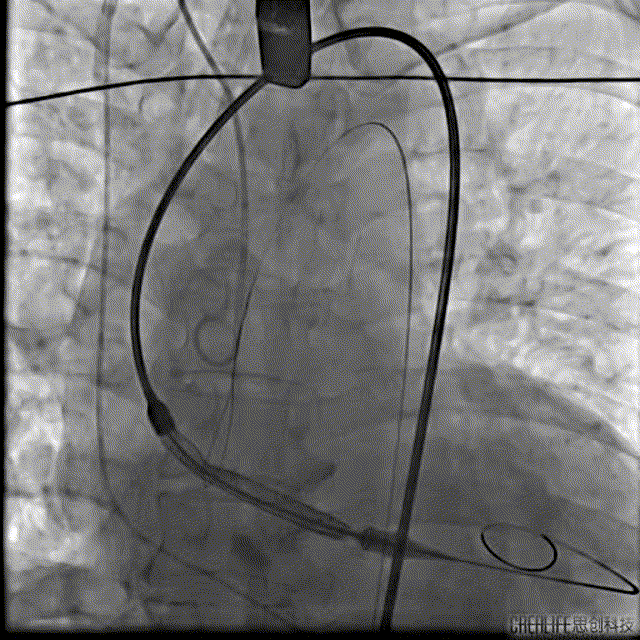

本例患者只有61岁,超声诊断低流速低压差AS,合并升主动脉扩张,CT下测量升主动脉超过50,原则上首选外科手术。但广东省人民医院大血管组会诊后考虑患者低流速低压差,行主动脉瓣和升主动脉置换术,手术风险极高,建议TAVR。从解剖上,瓣环流出道的大小分别是30、31,但瓣上结构是TYPE 0二叶瓣,重度钙化,联合部有钙化融合,瓣上短轴31,窦高度超过23,横位心,角度78°二叶瓣方向呈1点到7点方向。这种解剖做TAVR无疑挑战极大。对于低流速低压差的患者合并解剖挑战的病人,术前计划就是ecmo辅助下TAVR。考虑二叶瓣和重度钙化,目标瓣膜是29号,故用23号球囊预扩,尽量不破坏瓣上结构,另外考虑横位心,升主宽,破裂风险高,瓣膜跨瓣困难,故准备抓捕器辅助跨瓣。投照角度方面准备了瓣膜切线位(左肩),用来跨瓣和球扩,同时准备多一个右足位,这个角度下瓣环和人工瓣膜可以达到共平面,方便瓣膜定位。因为升主宽,横位心,主动脉迂曲,为减少破裂风险,没有选择plus。术中跨瓣遇到较大挑战,因为主动脉根部的角度大,普通的AL2,JR2,多功能导管均无法跨瓣,尝试直头导丝和弯头泥鳅也失败,最后是JL4加直头导丝成功跨瓣。预扩后瓣膜跨瓣尽管在抓捕器辅助下仍然非常困难,在反复尝试后侥幸跨瓣。瓣膜释放后位置偏深,但结合瓣膜角度,瓣周漏可以接受,压差消失,故未再行瓣中瓣。术中未发生停跳,故手术结束后撤去ECMO返回CCU。术后一个月随访EF值明显改善,患者自我感觉明显好转,虽然有中度瓣周漏,但是患者年轻,调整好心功能后,为以后外科置换升主动脉和主动脉瓣打下基础。

手术过程:

根部造影

Nmued 23扩张

VenusA 29瓣膜定位

VenusA 29瓣膜释放

最后一枪造影